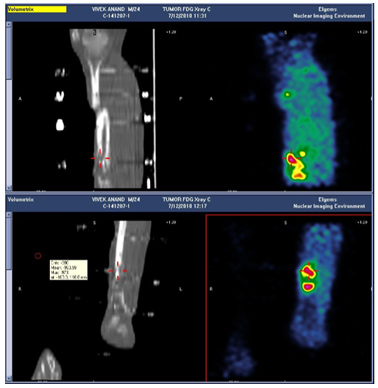

PET Scan

The FDG PET Scan showing active infection at the lower fracture site. An arterial DSA (Digital Subtraction Angiogram) was done to determine the course and patency of the arteries.